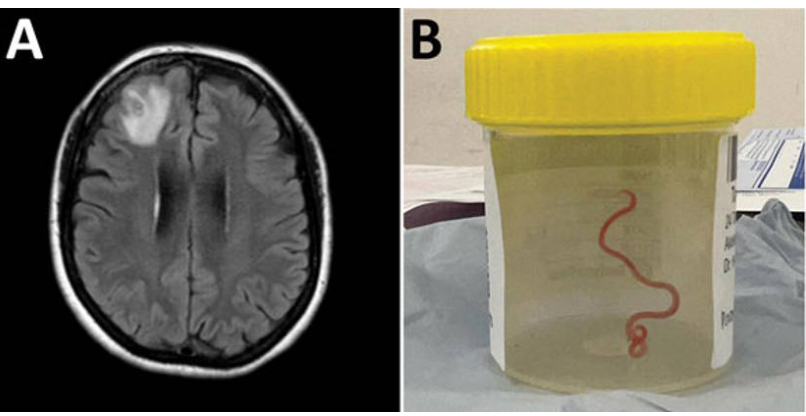

Sin embargo, la neurocirujana que abordó el caso, Hari Priya Bandi, encontró algo que parecía salido de una película de terror: un gusano parásito de 8 centímetros que aún estaba vivo y se retorcía. Finalmente, pudo extraerlo sin complicaciones.

El sorprendente descubrimiento llevó a un equipo del hospital a reunirse rápidamente para descubrir qué tipo de gusano redondo era y, lo más importante, decidir cualquier tratamiento adicional que pudiera requerir la paciente.

Tras buscar infructuosamente en todos los diferentes tipos de gusanos que podrían causar invasión neurológica y enfermedad, trataron de encontrar ayuda en expertos externos al hospital. Así, el gusano, que todavía estaba vivo, fue enviado directamente al laboratorio de un científico de CSIRO (Organización de Investigación Científica e Industrial del Commonwealth) que tenía mucha experiencia con parásitos.

Lo que certificó este experto es que el parásito era Ophidascaris robertsi, un gusano que se encuentra normalmente en serpientes pitones. La paciente del hospital de Canberra se convertía así en el primer caso en el mundo de este parásito encontrado en humanos.